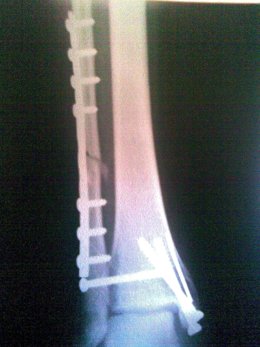

Las fracturas óseas tendrán tratamientos personalizados a partir del estudio de una radiografía, con la que se podrá determinar cómo se va a curar el hueso y qué va a necesitar el paciente. Estas son las primeras conclusiones del proyecto europeo CAD-BONE, liderado por un equipo del Instituto de Investigación en Ingeniería de Aragón (I3A) de la Universidad de Zaragoza (UZ).

Los principales resultados de este programa, a seis meses de finalizar, son el desarrollo de tratamientos específicos a medio y largo plazo, la creación de herramientas predictivas de remodelación y regeneración y la reconstrucción en 3D, según han informado desde la UZ.